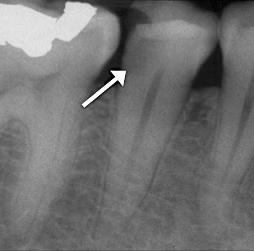

Obtaining a pretreatment pulpal and periradicular diagnosis before performing restorative treatment helps the clinician better understand how to treat the dental pulp, especially if it is exposed during caries excavation (Figure 1). A recent study by Ricucci et al found that a clinical pulpal diagnosis of a normal pulp or reversible pulpitis had a 96.6% histological match to the actual pulp tissue in a tooth.17 Therefore, for patients who present with or without pain from a carious pulp exposure and a pulp diagnosis of a normal pulp or reversible pulpitis, the tooth can be successfully treated with a mineral trioxide aggregate (MTA) pulp capping or pulpotomy if the pulp is exposed during treatment.18 In a randomized clinical trial, Hilton et al reported that MTA performed significantly better than calcium hydroxide as a direct pulp-capping agent.19

Fig 1. Obtaining a pretreatment pulpal and periradicular diagnosis prior to restorative treatment allows the clinician to properly treat the dental pulp if exposed during caries removal. Here, radiographic evidence of decay is shown on tooth No. 29 (arrow).

Figure 1